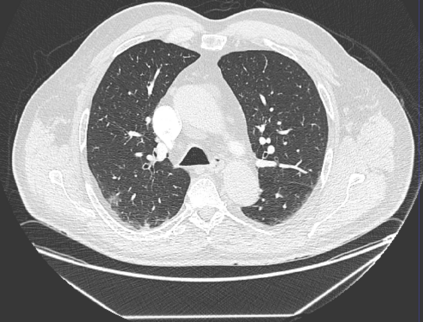

The COVID-19 pandemic has had a considerable impact on day-to-day life. Tackling the disease by providing the necessary resources to the affected is of paramount importance. However, estimation of the required resources is not a trivial task given the number of factors which determine the requirement. This issue can be addressed by predicting the probability that an infected patient requires Intensive Care Unit (ICU) support and the importance of each of the factors that influence it. Moreover, to assist the doctors in determining the patients at high risk of fatality, the probability of death is also calculated. For determining both the patient outcomes (ICU admission and death), a novel methodology is proposed by combining multi-modal features, extracted from Computed Tomography (CT) scans and Electronic Health Record (EHR) data. Deep learning models are leveraged to extract quantitative features from CT scans. These features combined with those directly read from the EHR database are fed into machine learning models to eventually output the probabilities of patient outcomes. This work demonstrates both the ability to apply a broad set of deep learning methods for general quantification of Chest CT scans and the ability to link these quantitative metrics to patient outcomes. The effectiveness of the proposed method is shown by testing it on an internally curated dataset, achieving a mean area under Receiver operating characteristic curve (AUC) of 0.77 on ICU admission prediction and a mean AUC of 0.73 on death prediction using the best performing classifiers.